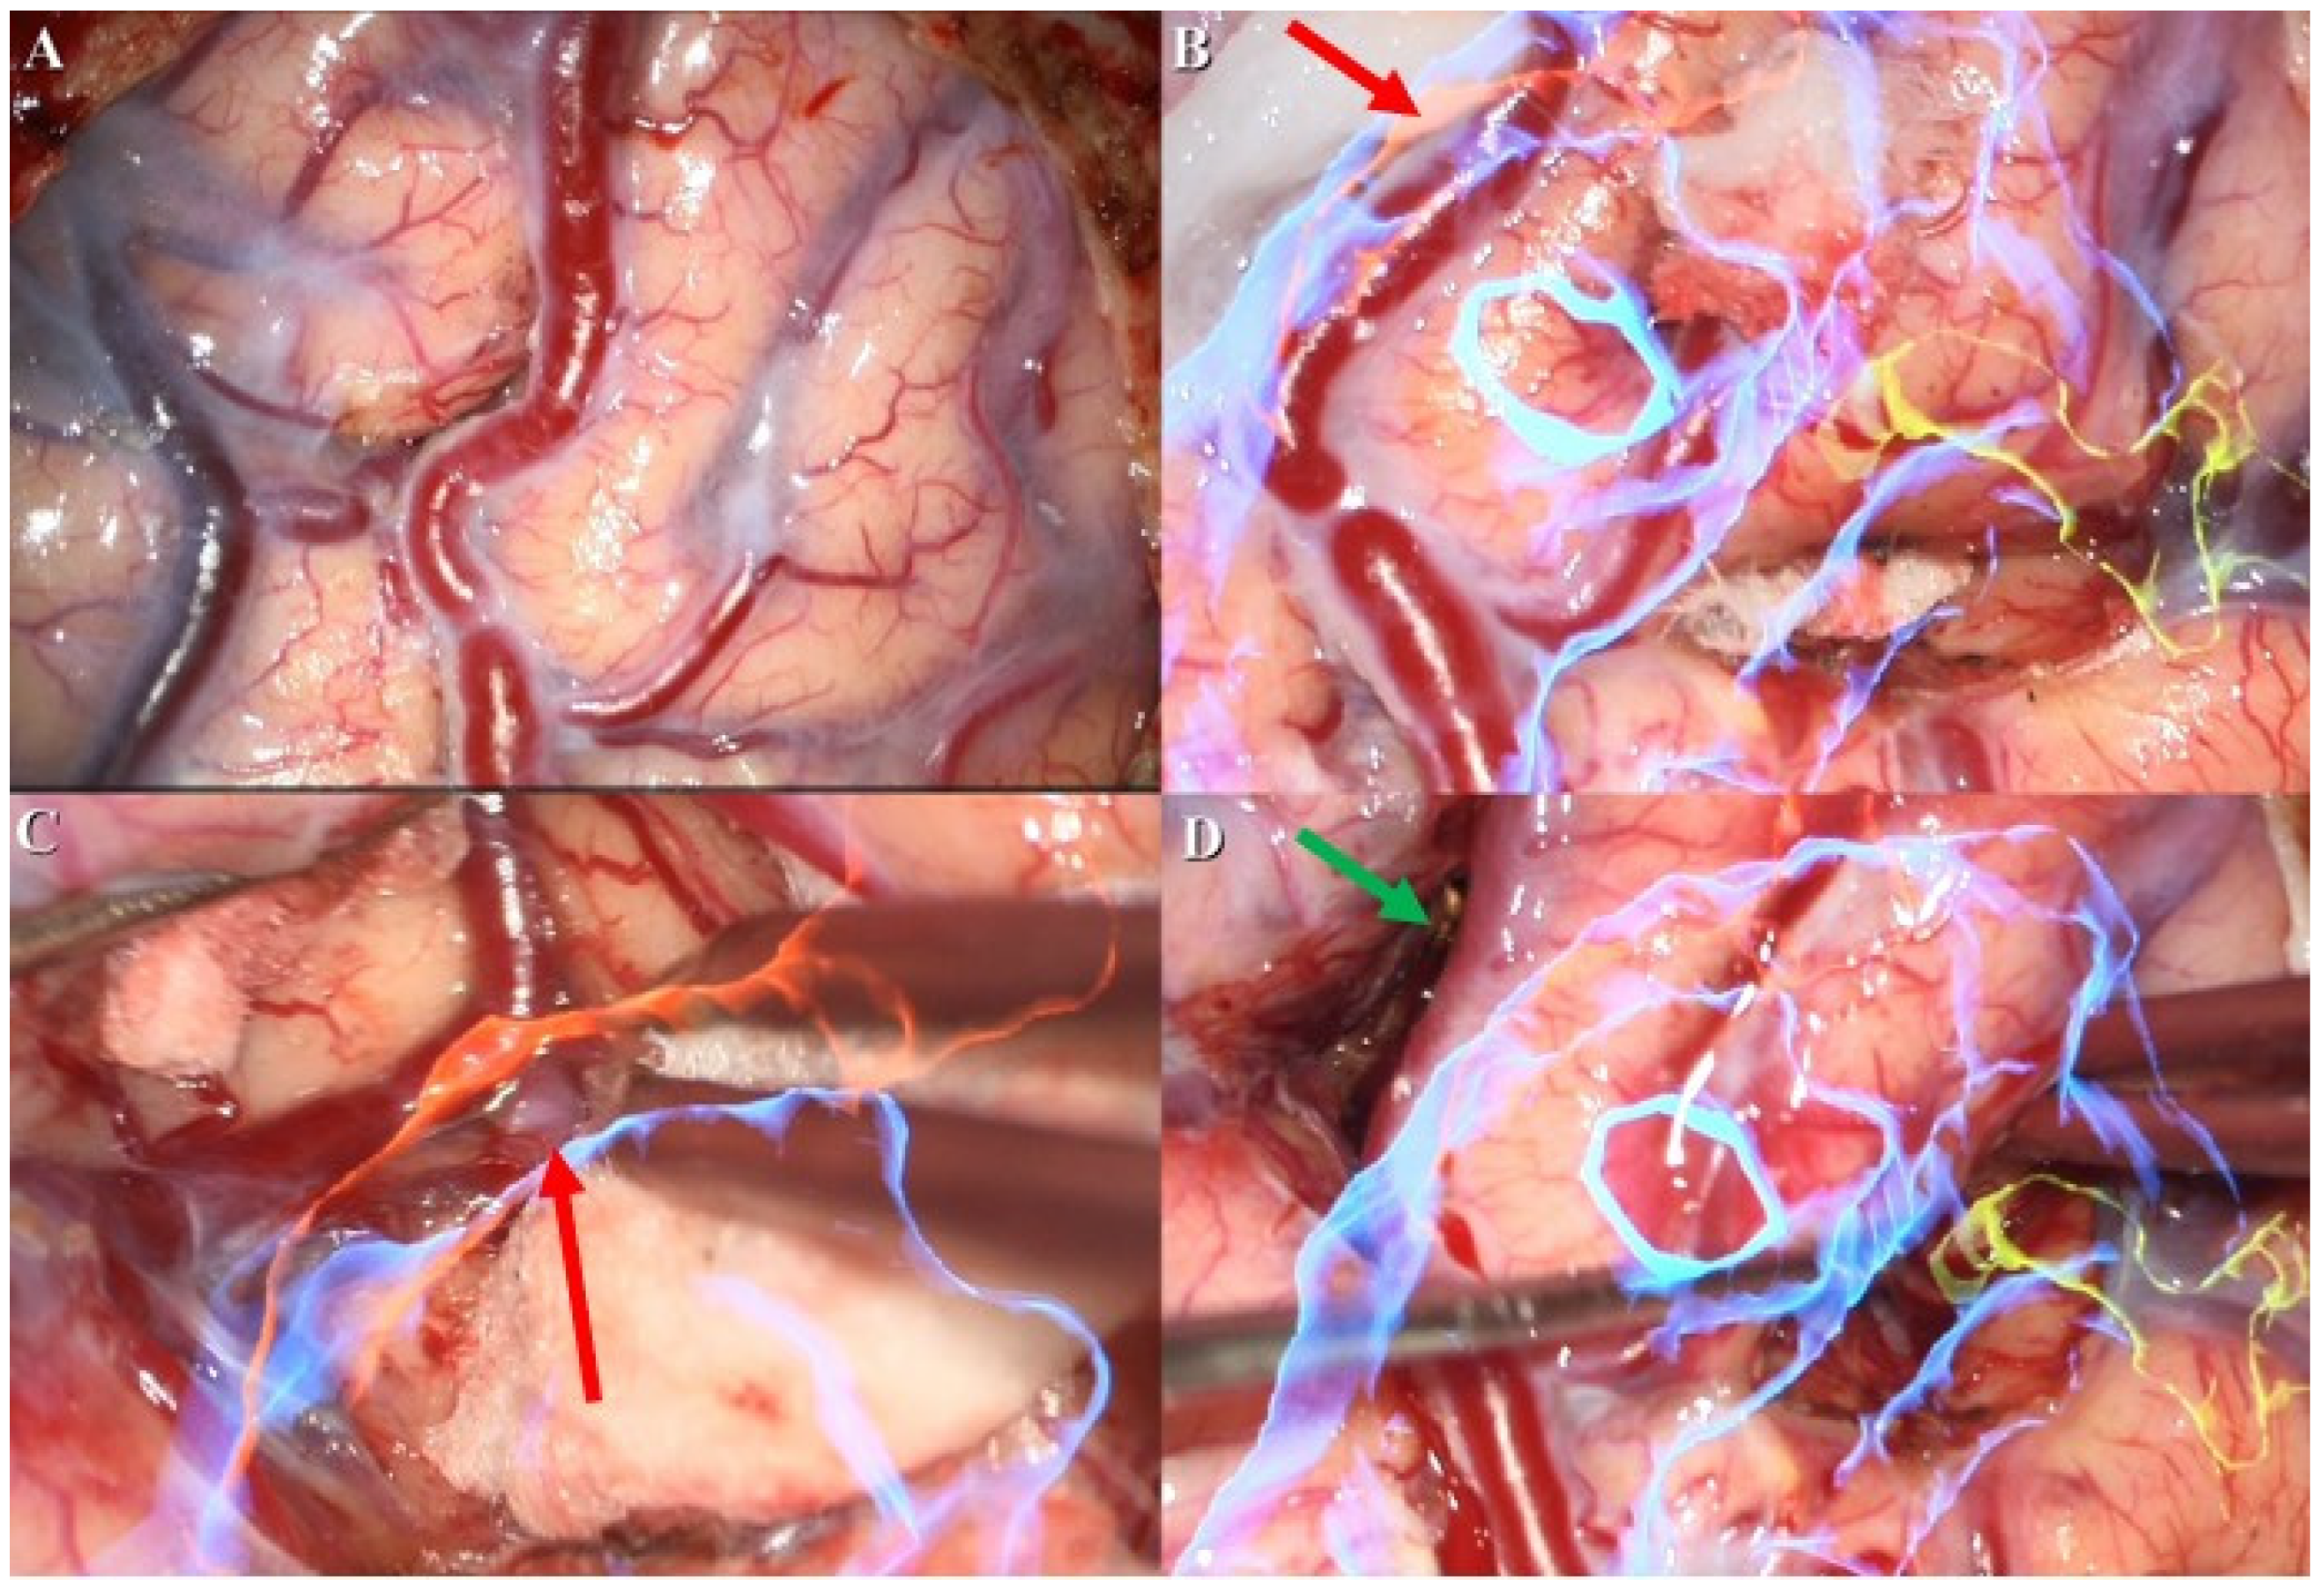

The first stage of the operation for the patient’s AVM resection was confirmative digital subtraction angiography (DSA) (Figure 1D) followed by right parieto-occipital craniotomy. After performing a dura opening, surgery proceeded to the microsurgical stage performed under a microscope (Figure 2A). With assistance from the AR technique, the feeding arteries from the posterior cerebral artery and the parietal branch of the middle cerebral artery were labeled with red and yellow color, respectively, and then projected onto the cortex. Furthermore, the AVM nidus was coded with blue color for identification (Figure 2B). In the next dissection and resection stage, we adjusted the focal length and hologram setting to clarify the surgical field. After confirmation of the spatial relationship in the angiographic complex, both coagulation and clipping were performed to obliterate the feeding artery (Figure 2C). After the clipping and coagulation of the first feeding artery from the middle cerebral artery, we proceeded to obliterate another feeding artery from the posterior cerebral artery (Figure 2D). Eventually, the AVM nidus got resected after both the feeding arteries were obliterated.

Figure 2. Microsurgery under assistance of AR technique. (A) Surgical field without AR hologram projection. (B) AVM nidus and feeding arteries were labeled with different color (blue: AVM nidus; red: feeding artery from middle cerebral artery; yellow: feeding artery from posterior cerebral artery); the red arrow also indicates feeding artery from middle cerebral artery. (C) Clipping and coagulation of the feeding artery. (D) Obliteration for another feeding artery from posterior cerebral artery; the green arrow indicates clip for feeding artery elimination.